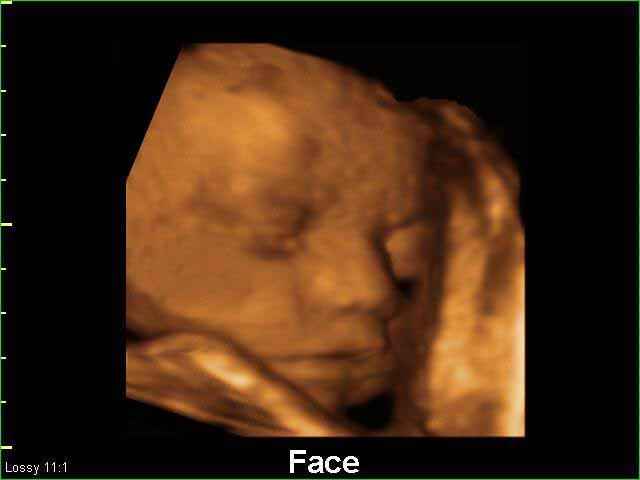

3D Fetal Face Ultrasound Scan Photos